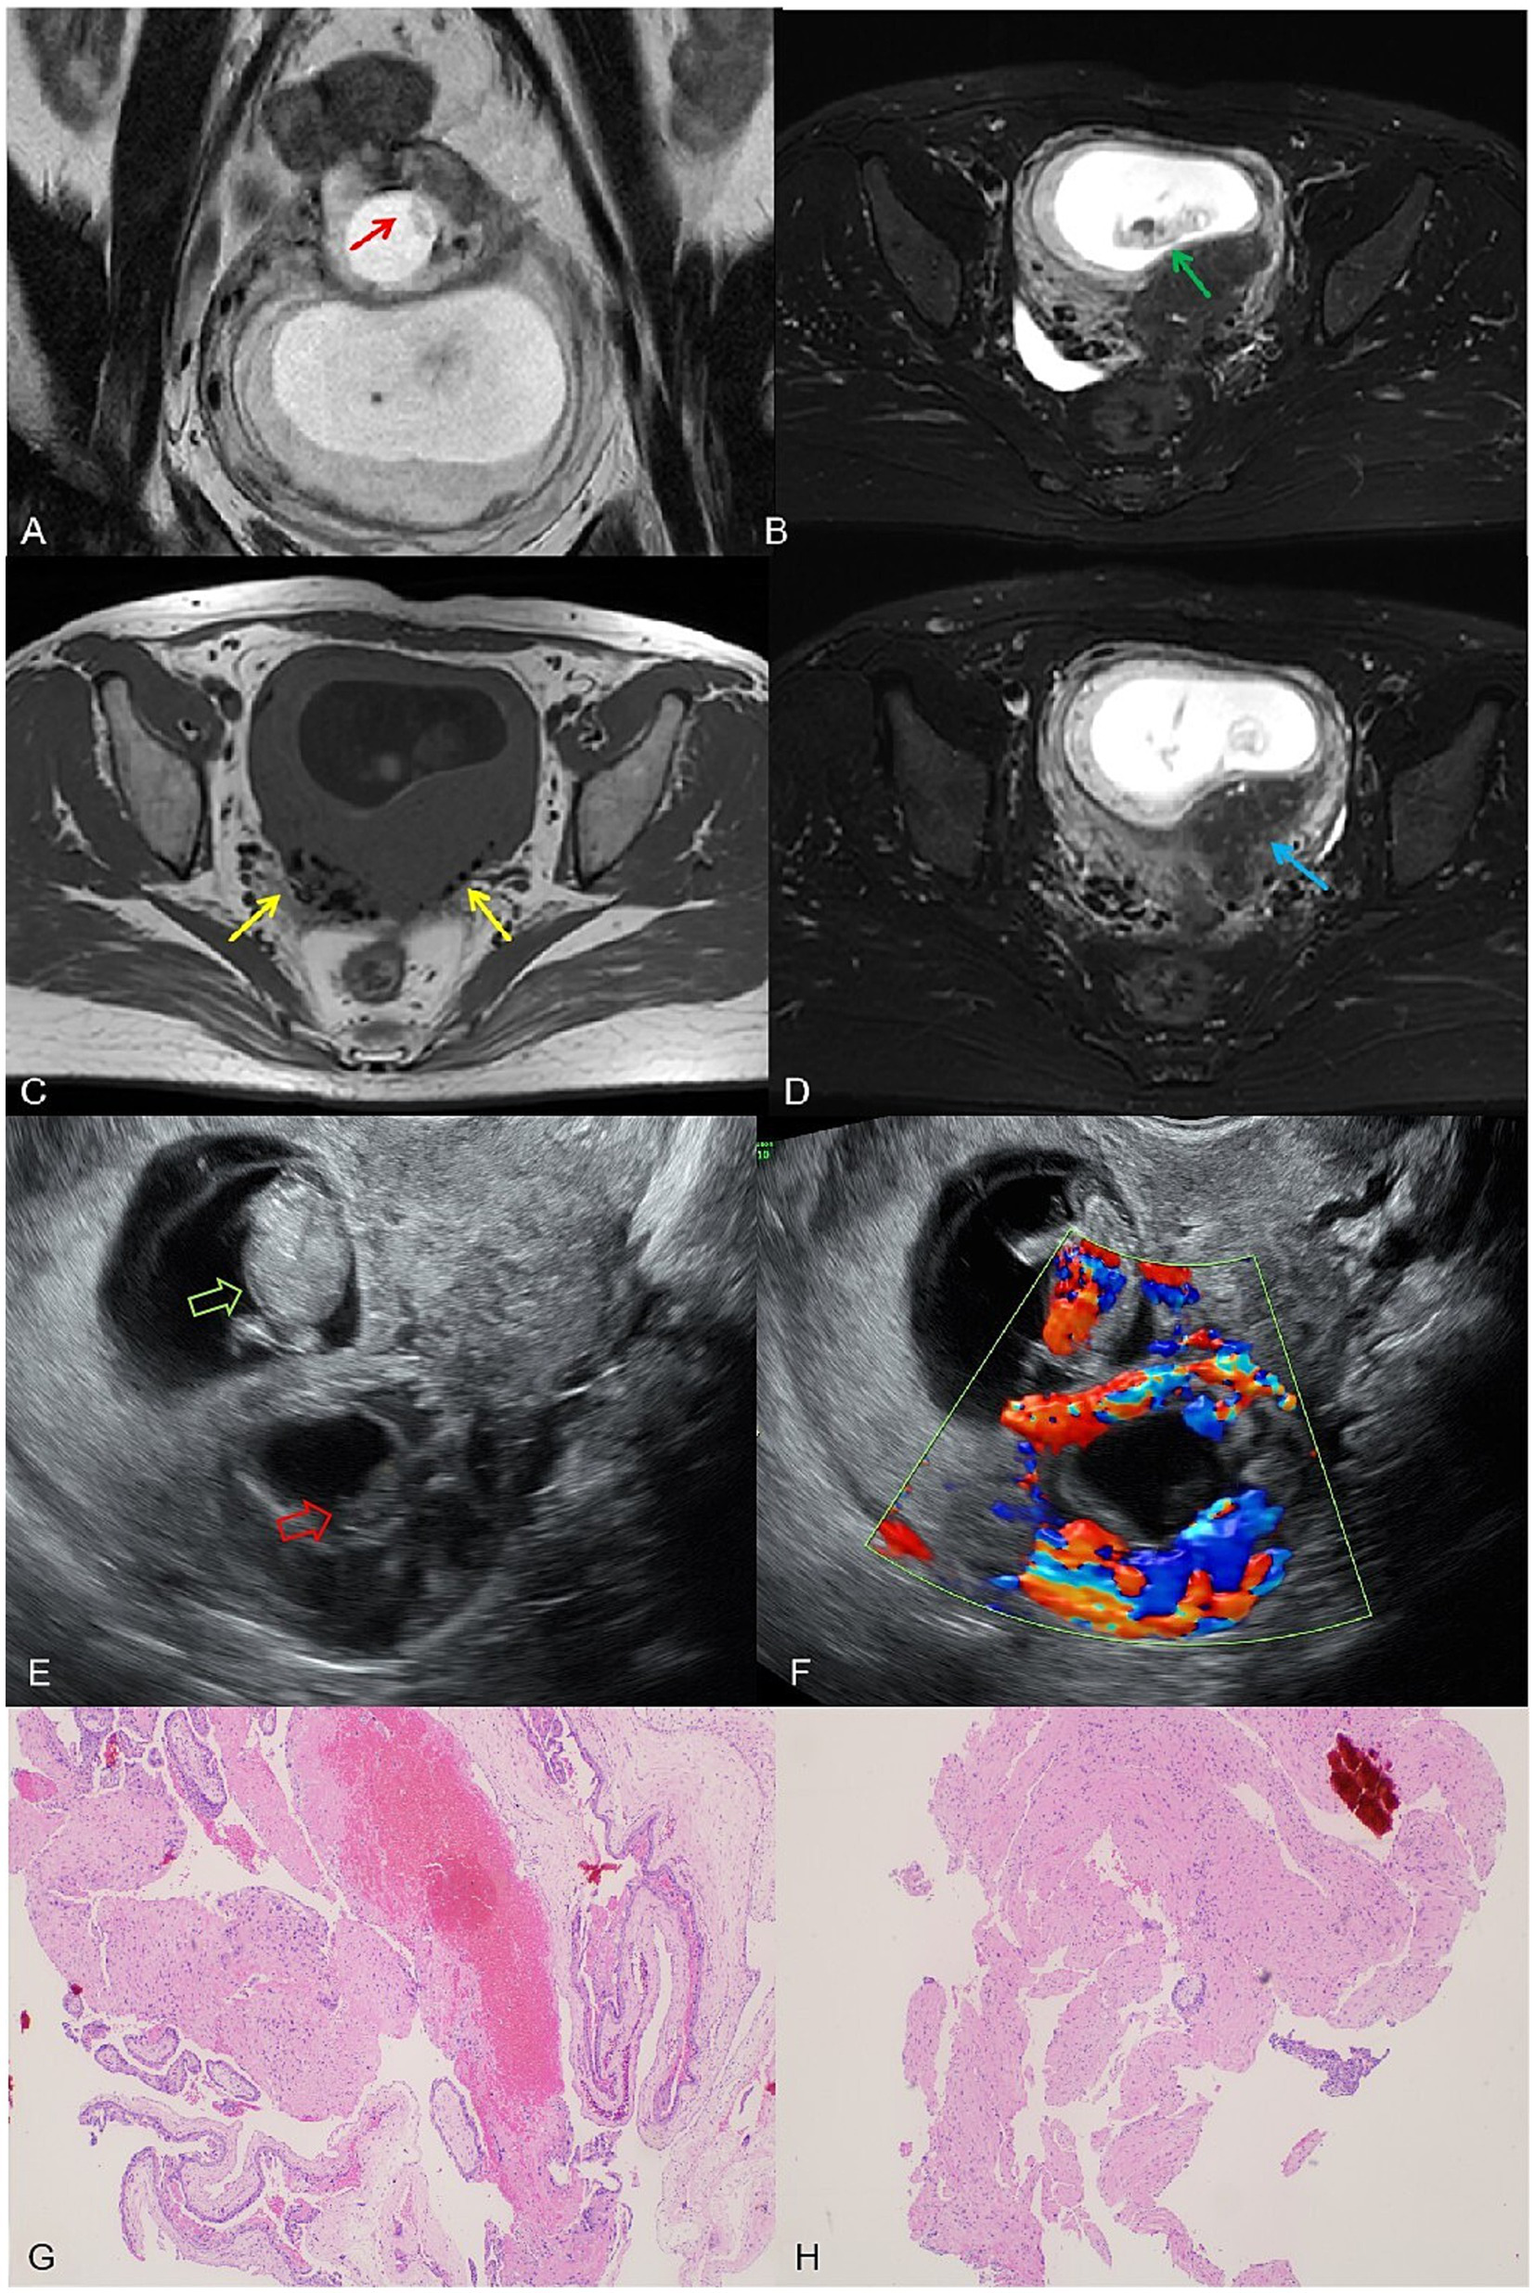

On 14 March 2024, the patient underwent another embryo transfer. At 13th April (31 days post-transfer), ultrasound confirmed an intrauterine pregnancy (gestational sac 24.4 × 22.2 × 12.9 mm, embryo 7.2 mm) with slight bleeding. At 10 weeks (day 69 post-transfer), a 1.5 T MRI (United Imaging uMR560) confirmed an intrauterine pregnancy (gestational sac 62 × 41 × 70 mm, CRL 34 mm) but initially misidentified a 23 × 22.7 × 21 mm intramural pregnancy as cystic adenomyosis. Routine T2-FSE sequences obscured the intramural embryo, but a smaller-field T2-FSE revealed an 8.9 mm embryo in the intramural sac. A 3D T1 axial sequence partially depicted the embryo despite moderate signal limitations (Figure 2).

Figure 2

(A) A complete embryonic bud, measuring 8.9 mm, visible within the intramural gestational sac on the small T2 FSE sequence (red arrow). (B) A normal intrauterine pregnancy with a fetus measuring a crown-rump length of 34 mm on the T2-fs-FSE sequence (yellow arrow). (C) T1WI shows black speckled hypointense signals, considering postoperative changes (red arrow). (D) T2-FSE-SPAIR reveals residual adenomyosis with visible small cysts (yellow arrow). (E) Ultrasound image shows the intrauterine pregnancy fetus (green hollow arrow) and the intramural pregnancy fetus (red hollow arrow). (F) Color Doppler ultrasound image: cardiac activity detected in the intrauterine fetus, but absent in the intramural fetus; ring-shaped blood flow signals can be observed around the intramural gestational sac. (G,H) Postoperative pathological slides showing chorionic tissue (hematoxylin and eosin stain, magnification ×40).

On the same day, transvaginal ultrasound showed an enlarged intrauterine sac (38.9 × 57.6 × 65 mm) with an embryo (CRL 38.9 mm) and cardiac activity. A smaller posterior myometrial lesion (23.7 × 18.9 mm) contained a 10.7 mm embryo-like structure without a yolk sac or cardiac activity, which was attached to the serosal layer with minimal myometrium and abundant blood flow. A 43.6 × 34.4 × 54.3 mm fluid-filled cystic area was noted near the right ovary. These findings led to a multidisciplinary MRI review, which confirmed intramural ectopic pregnancy. MRI also revealed adenomyosis, minor cystic changes in the lower uterine segment, and postoperative scarring (low-signal areas). The cervix measured 37 mm, showing stromal thickening likely due to pregnancy hormones. The patient underwent exploratory laparotomy under combined spinal-epidural anesthesia. A 5 × 4 cm intramural mass was found on the posterior uterine wall, densely adhered to the surrounding tissues. After careful adhesiolysis, the ectopic gestational tissue was excised from the myometrium, and the uterus was repaired in two layers with absorbable sutures. Both fallopian tubes were absent due to prior bilateral salpingectomy. Intraoperative blood loss was approximately 200 mL. The patient had an uneventful recovery and was discharged in stable condition.